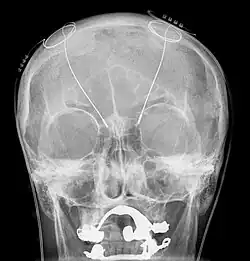

Układ do głębokiej stymulacji mózgu składa się z trzech elementów: wszczepionego generatora rytmicznej czynności elektrycznej (właściwego „rozrusznika”), doprowadzenia sygnału do odpowiedniego jądra mózgu i połączenia. Generator jest zasilanym przez baterię neurostymulatorem umieszczonym w tytanowej obudowie, wysyłającym sygnały elektryczne do mózgu, które oddziałują z czynnością elektryczną neuronów w określonym docelowo jądrze mózgowym. Sygnał do mózgu doprowadza metalowy przewód pokryty izolującą osłonką poliuretanową, zakończony czterema małymi elektrodami platynowo-irydowymi, które umieszcza się w wybranym miejscu mózgu. Doprowadzenie to jest połączone z generatorem izolowanym przewodem wychodzącym przez czaszkę na zewnątrz głowy i biegnącym dalej za uchem na szyję, a następnie do dołu podobojczykowego, gdzie najczęściej neurochirurg umieszcza generator[6].